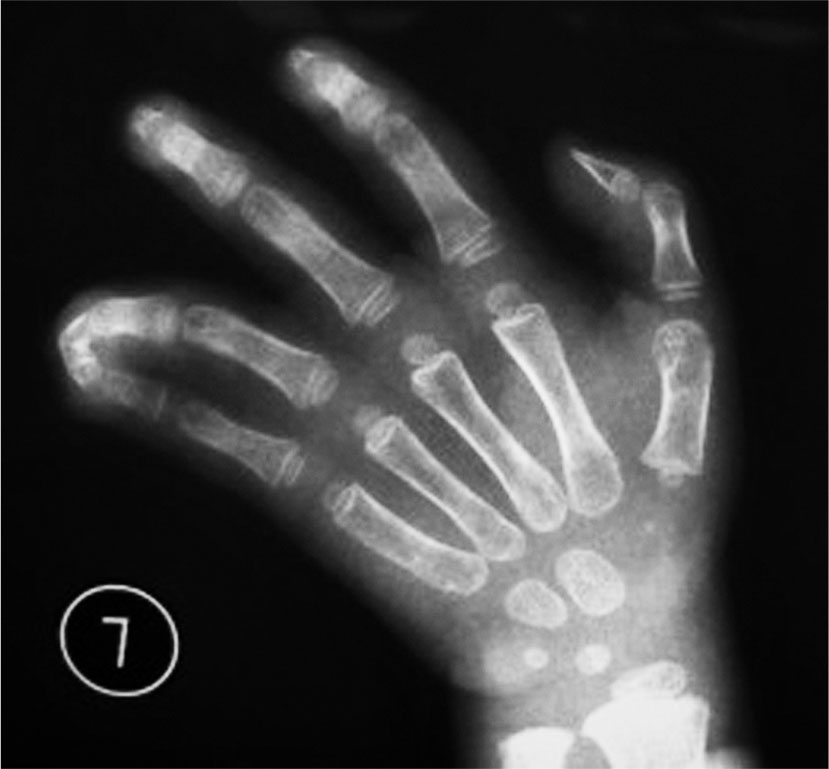

A.双手手指短小(右侧中、小指,左侧示、小指);B.X 线片显示右侧第Ⅲ、Ⅴ掌骨短小,左侧第Ⅴ掌骨短小,左示指中节指骨、双小指中节指骨短小;C.患手握拳时可见掌骨短小的手指掌指关节塌陷,关节屈曲受限

1.短指并指畸形(图1-2-46)。